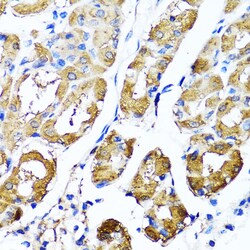

Immunogen sequence: RWAFNWDTKD IYRQRSRALV QAQHPDWPAP QVEAVAQDQF QGAARAWMAG TLQLGRALRP RGLWGFYGFP DCYNYDFLSP NYTGQCPSGI RAQNDQLGWL WGQSRALYPS IYMPAVLEGT GKSQMYVQHR VAEAFRVAVA AGDPNLPVLP YVQIFYDTTN HFLPLDELEH SLGESAAQGA AGVVLWVSWE NTRTKESCQA IKEYMDTTLG PFILNVTSGA LLCSQALCSG HGRCVRRTSH PKALLLLNPA SFSIQLTPGG GPLSLRGALS LEDQAQMAVE FKCRCYPGWQ APWCERKSMW; Positive Samples: Mouse liver, Mouse lung; Cellular Location: Lysosome.

This gene encodes a lysosomal hyaluronidase. Hyaluronidases intracellularly degrade hyaluronan, one of the major glycosaminoglycans of the extracellular matrix. Hyaluronan is thought to be involved in cell proliferation, migration and differentiation. This enzyme is active at an acidic pH and is the major hyaluronidase in plasma. Mutations in this gene are associated with mucopolysaccharidosis type IX, or hyaluronidase deficiency. The gene is one of several related genes in a region of chromosome 3p21.3 associated with tumor suppression. Multiple transcript variants encoding different isoforms have been found for this gene.

| ELISA, Immunohistochemistry (Paraffin), Western Blot, Immunocytochemistry | |

| Recombinant fusion protein containing a sequence corresponding to amino acids 136-435 of human HYAL1 (NP_1493492). | |